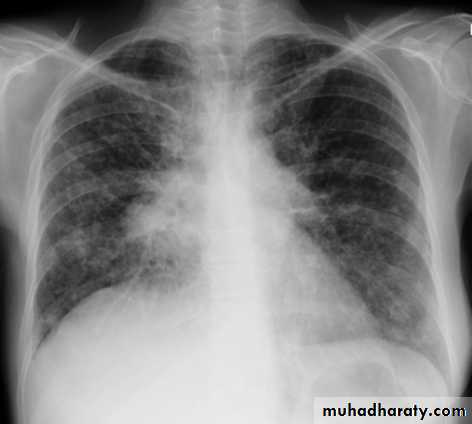

Congestive cardiac failure (CCF) is a form of cardiac failure which is primarily manifested by the heart inability to pump the volume of blood. It can affect the left (common) or right cardiac chambers or both.

Radiographic features

Chest radiograph

With left sided congestive cardiac failure, the features are that of pulmonary edema which includes:

central pulmonary venous congestion ( prominent hilum )

cephalization of pulmonary veins ( upper lobe pulmonary venous diversion )

pulmonary interstitial edema

pulmonary alveolar edema

Cardiomegaly

Pleural effusion